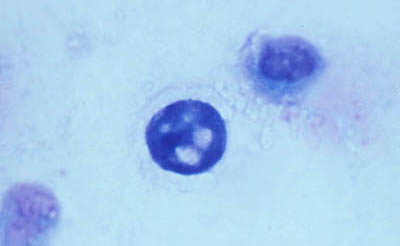

Frotis - extendido en capa

Preparaciones de extendido en capa sobre laminilla con agua destilada sin colorear, en campo claro y bajo contraste de fases: permite buena visualización de las formas Quísticas de Acanthamoeba

Magnificación 160x

Tinción Giemsa

Magnificación 160x